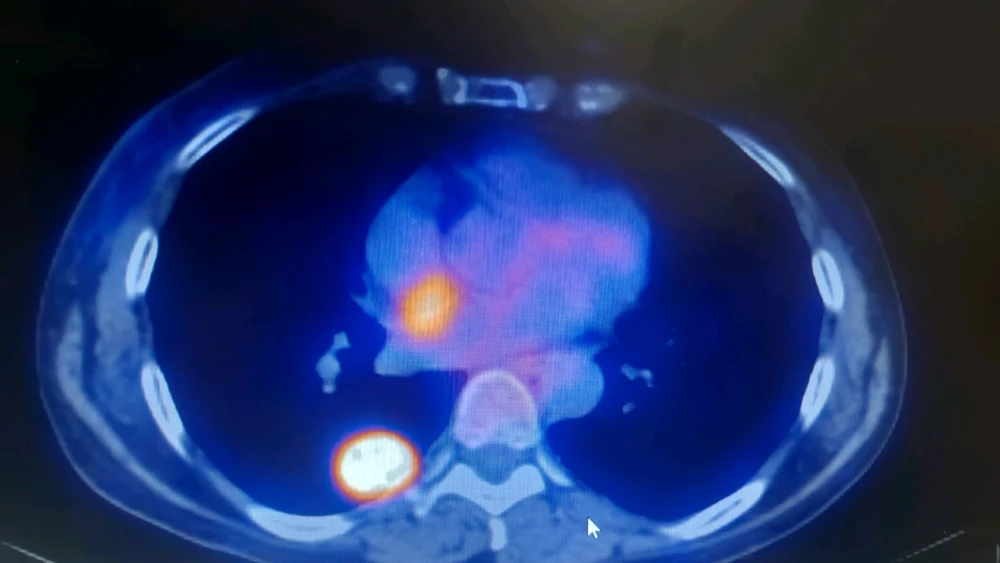

Nodulo pulmonar solitario en segmento superior de lóbulo inferior derecho (LID). A esto en radiología se le puede llamar de varias maneras, por ejemplo condensación pulmonar con bronquio abierto (el puntito negro que se ve en la imagen más blanca) en contacto con pleura (está pegada a pared... leer más